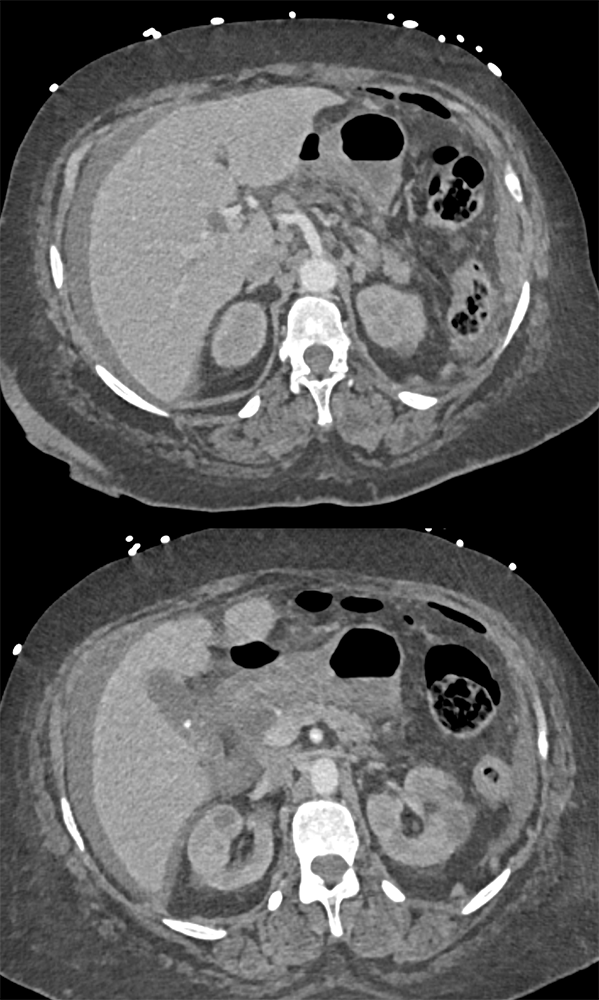

“In our patient, the findings of prominent mucosal folds extending from the pylonic channel on upper gastrointestinal series and the thickened antral wall on CT scans correlate well with the known pathologic appearance of gastnic antral vascular ectasia. Histologically, antral thickening results from a combination of foveolar and fibromuscular hyperplasia. Grossly, the antral fold prominence appears to result from bunching of the mucosa in the thickened, hypercontractile antrum.” Gastric antral vascular ectasia ("watermelon stomach"): radiologic findings. Urban BA, Jones B, Fishman EK, Kern SE, Ravich WJ. Radiology. 1991 Feb;178(2):517-8. |

“Gastric antral vascular ectasia primanily affects women (9:1 female-to-male ratio) aged 56-76 years, and is associated with liver cirrhosis (37%) and achlorhydnia (35%). The usual symptoms are iron-deficiency anemia and melena due to chronic gastrointestinal bleeding from the dilated, superficial, and easily traumatized vessels. Antrectomy is curative, but endoscopic treatment with heat probes or lasers has shown promise.” Gastric antral vascular ectasia ("watermelon stomach"): radiologic findings. Urban BA, Jones B, Fishman EK, Kern SE, Ravich WJ. Radiology. 1991 Feb;178(2):517-8. |